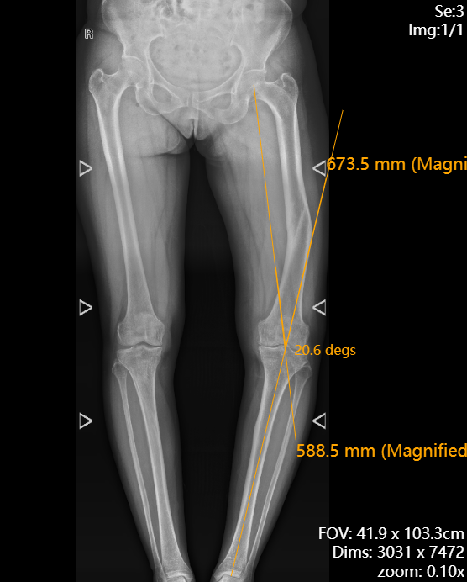

经过检查发现,她的膝盖已经明显内翻(膝盖往里歪),关节间隙一边窄一边宽,常规手术很难兼顾假体安装精度和膝盖稳定性,手术难度不小。

手术前,机器人系统先给王女士进行 CT 三维建模和个性化手术规划,把股骨远端的旋转角度、关节线倾斜程度、骨缺损情况都 “算” 得明明白白,就像给膝盖画了一张 “精准地图”。

术后复查显示,王女士双下肢的力线恢复正常,膝盖伸直、弯曲都能动态平衡,假体固定得稳稳的。